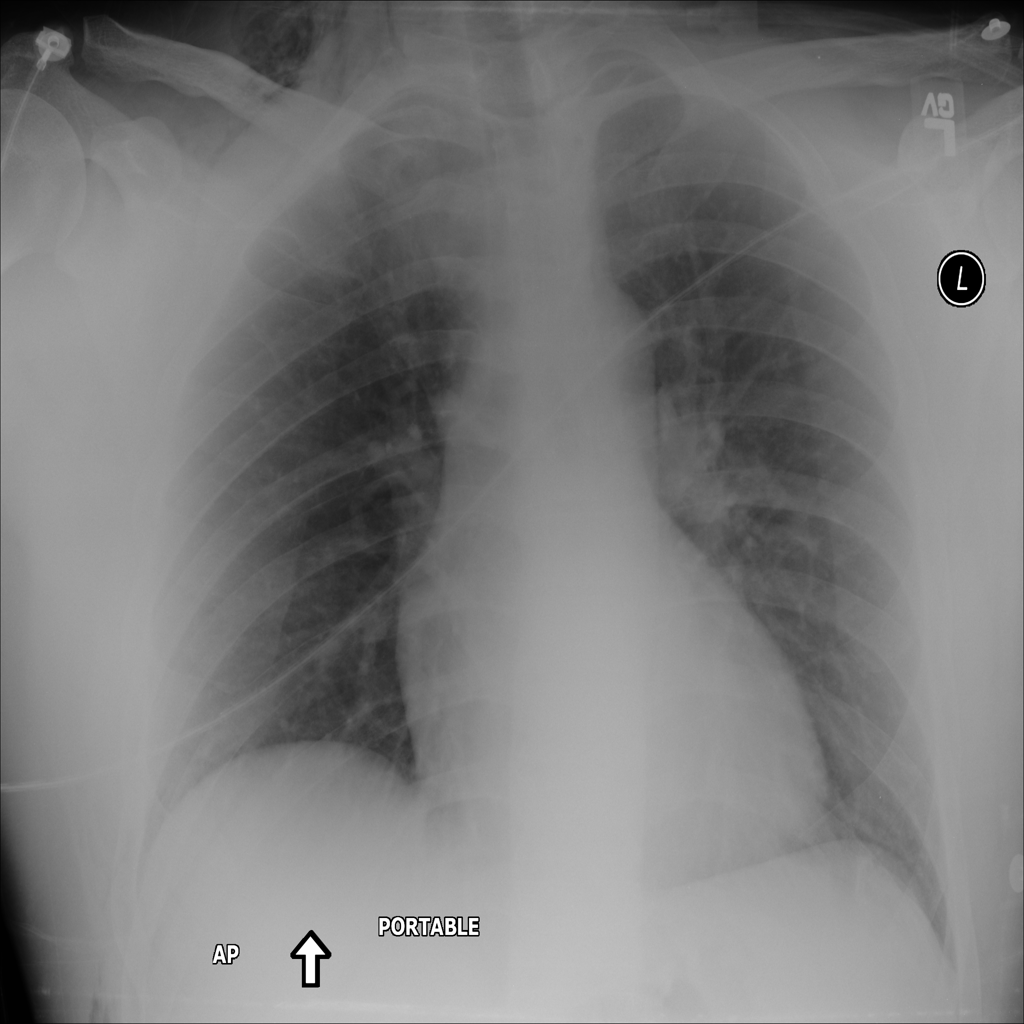

PAT-B0DB · IMG-003Emphysema

PAT-B0DB · IMG-003

PA